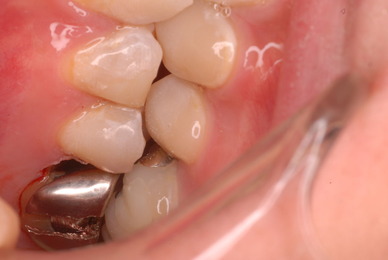

入れ歯の話から入りました。色々不満で注文があるようです。でも話が一段落して口腔内を調べると殆どの歯が重症で抜けそうな歯だらけなのです。

ご自分でやられても歯茎から血が出ないと話をされていましたが、私がブラシを当てると悲惨な状態であることがわかりました。